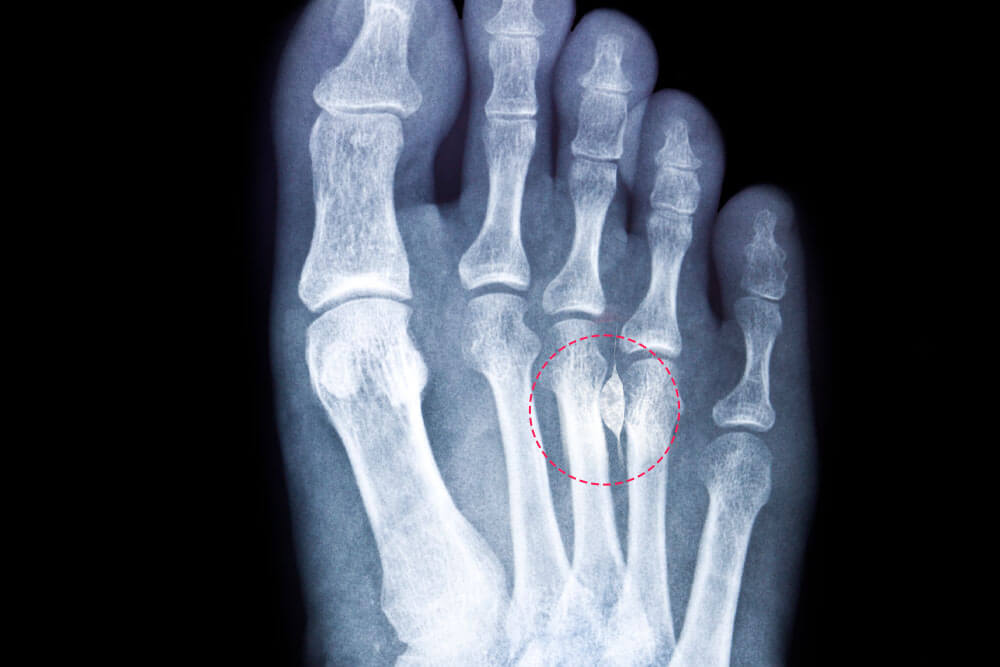

Неврома Мортона — это не рак. И даже не "настоящая" опухоль в онкологическом смысле. Это доброкачественное утолщение (фиброз) тканей вокруг плантарного нерва, чаще всего в третьем межплюсневом промежутке (между основаниями 3-го и 4-го пальцев). Нерв как бы зажат, сдавлен между головками плюсневых костей и глубокой поперечной плюсневой связкой, что вызывает его хроническое раздражение, воспаление и последующее утолщение периневральных тканей. В принципе, это компрессионная невропатия, специфическая для переднего отдела стопы. Например, статистика показывает, что метатарзалгия, вызванная невромой Мортона, в 8-10 раз чаще встречается у женщин 35-60 лет, что напрямую связывают с ношением обуви на высоком каблуке и с узким носком, а также с такими состояниями, как поперечное плоскостопие или hallux valgus, которые изменяют биомеханику стопы и увеличивают давление на плюсну.

Допустим, вы заподозрили у себя проблему и обратились к врачу (ортопеду, травматологу). Что будет? Диагностика начинается с тщательного клинического осмотра стопы. Врач проведет пальпацию межплюсневых промежутков, оценит пульсацию сосудов, чувствительность и двигательную функцию пальцев, и обязательно выполнит специфические тесты: